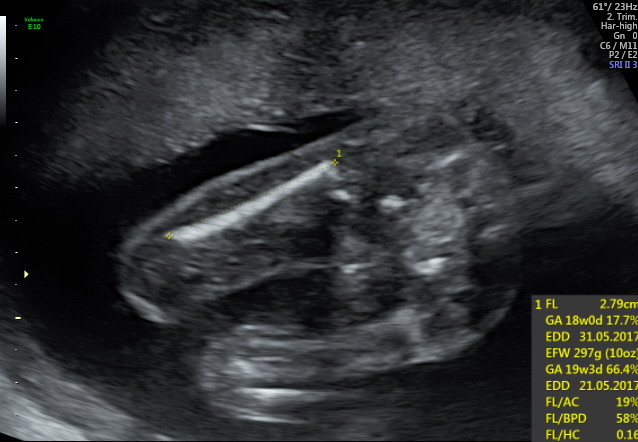

Hell All, as a soon to be first time dad, I've spent hours looking at the ultrasounds trying to determine the gender or the baby.

I obviously did this once I had found out both mom and bub are perfectly healthy. My wife and I decided we would find out the gender from our obstetrician, but the suspense is killing me.

Because of this we don't have a 'clear' potty shot, but I believe I have found boy bits on 3 other images. I haven't shown my wife this pictures and expressed my guess (nor am I going to) as I know she doesn't want to know,

I'm interested in seeing if my uneducated guess is correct?

don't really have a preference being first child, I think that image on the left is quite clear though? it outlines penis and two obvious 'circles' with 'cords' attached?? what makes you suggest girl?

Because, of the three lines. Could definitely be wrong though. Others will chime in soon that are really good with genders.

I'm leaning toward girl on this one. The potty shot shows 3 lines, although potty shots are not as accurate at this gestation.

I too am leaning more girl than boy but am no expert 😆